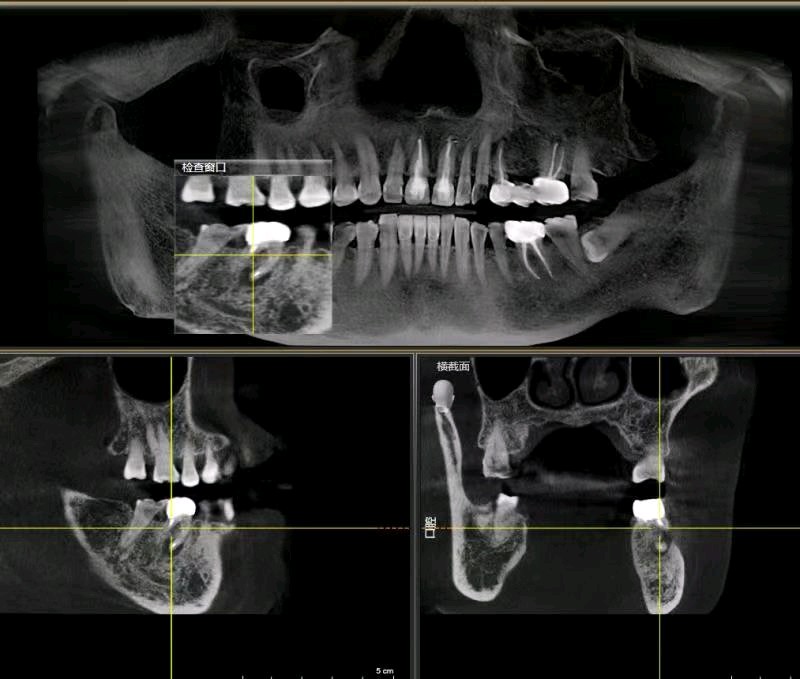

患者右下后牙根管治疗十年后咬合不适,x片显示近中根尖阴影较大,根折,患牙不能保留,患者非常焦虑拔牙,更怕种植牙,要求拔牙后即刻种植,通过CBCT检查,确定剩余骨量足够多,可以即拔即种植;患者知情同意下,完成即拔即种,四个月后CEREC数字化扫描,当天完成了牙冠修复,同时邻牙也完成嵌体修复!有图有真相。